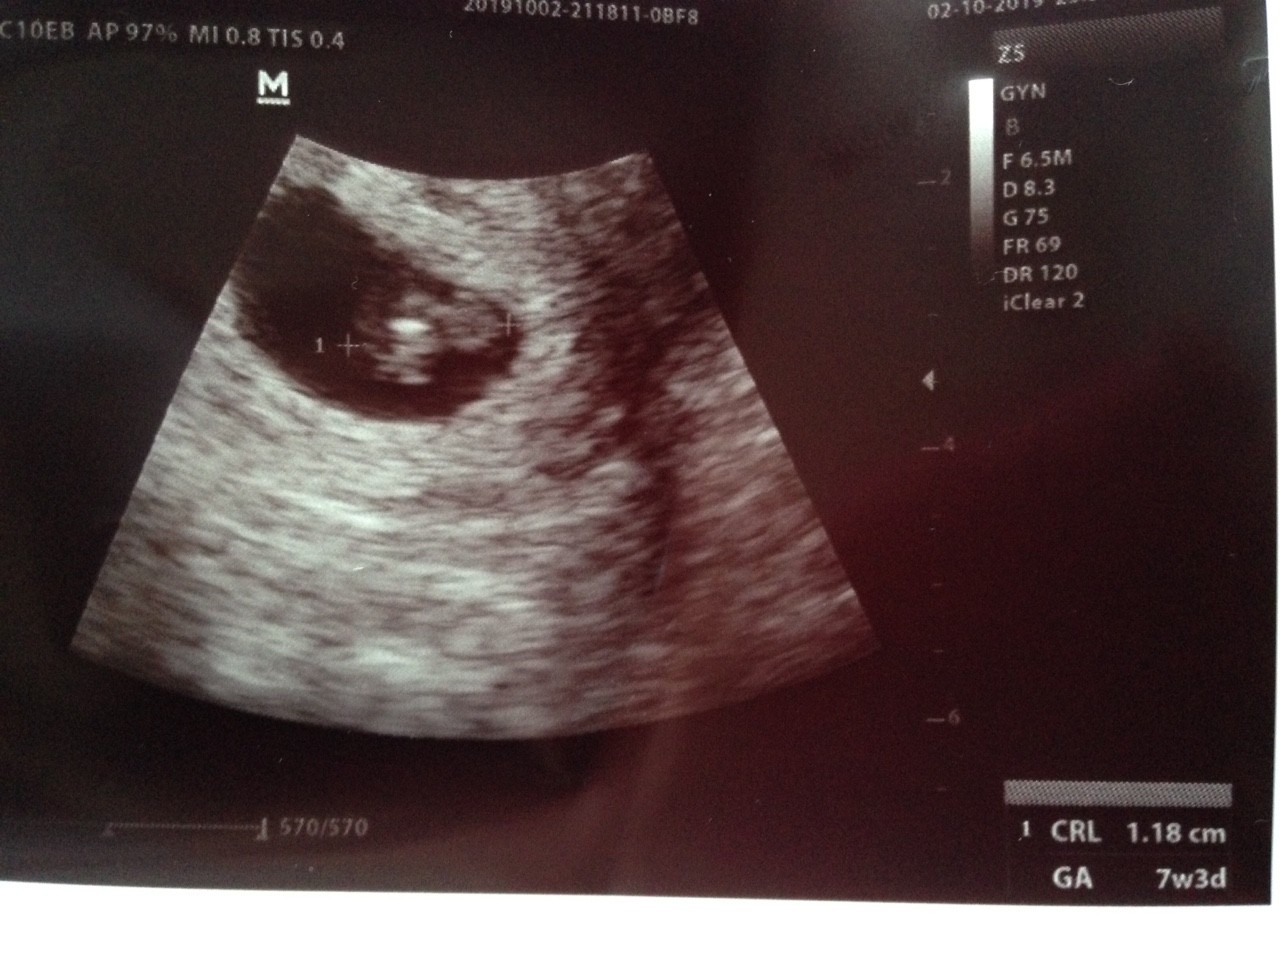

Już po wizycie! Jest czynność serca Puls 145 na minutę. Od ostatniej miesiączki jestem w 6+3 A według usg to 7+3.

Zrozumiałam że mój Maluszek ma 7 mm ale teraz na usg widzę CRL 1,18.

PS. Ta biała plamka to serduszko

Teraz tak :) cudo!